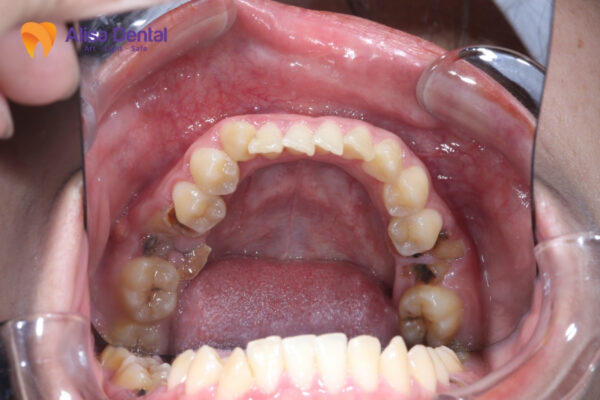

Dấu Hiệu Nhận Biết Sâu Răng Số 7 Sớm

Việc phát hiện sớm các dấu hiệu sâu răng số 7 là vô cùng quan trọng để có biện pháp điều trị kịp thời, tránh những biến chứng nghiêm trọng có thể xảy ra. Dưới đây là những dấu hiệu điển hình mà bạn cần chú ý:

Giai đoạn sâu răng tiến triển

- Đau nhức khi nhai, đặc biệt khi ăn thực phẩm cứng

- Ê buốt rõ rệt khi tiếp xúc với thức ăn nóng lạnh

- Xuất hiện lỗ sâu có thể nhìn thấy bằng mắt thường

- Thức ăn thường xuyên bị mắc kẹt tại vùng răng bị sâu

- Hơi thở có mùi hôi bất thường

Giai đoạn sâu răng nặng

- Đau nhức dữ dội, có thể lan tỏa sang vùng má và tai

- Sưng nướu xung quanh răng bị sâu

- Có thể xuất hiện mủ và áp xe quanh chân răng

- Đau đột ngột vào ban đêm, ảnh hưởng đến giấc ngủ

- Khó khăn trong việc nhai và ăn uống

Điều quan trọng cần lưu ý là sâu răng số 7 thường khó phát hiện trong giai đoạn đầu do vị trí của răng nằm sâu trong khoang miệng. Nhiều người chỉ nhận ra khi răng đã bị sâu khá nặng và gây đau đớn. Do đó, việc khám răng định kỳ 6 tháng/lần tại các cơ sở nha khoa uy tín như Nha khoa Alisa là rất cần thiết để phát hiện sớm các vấn đề răng miệng.